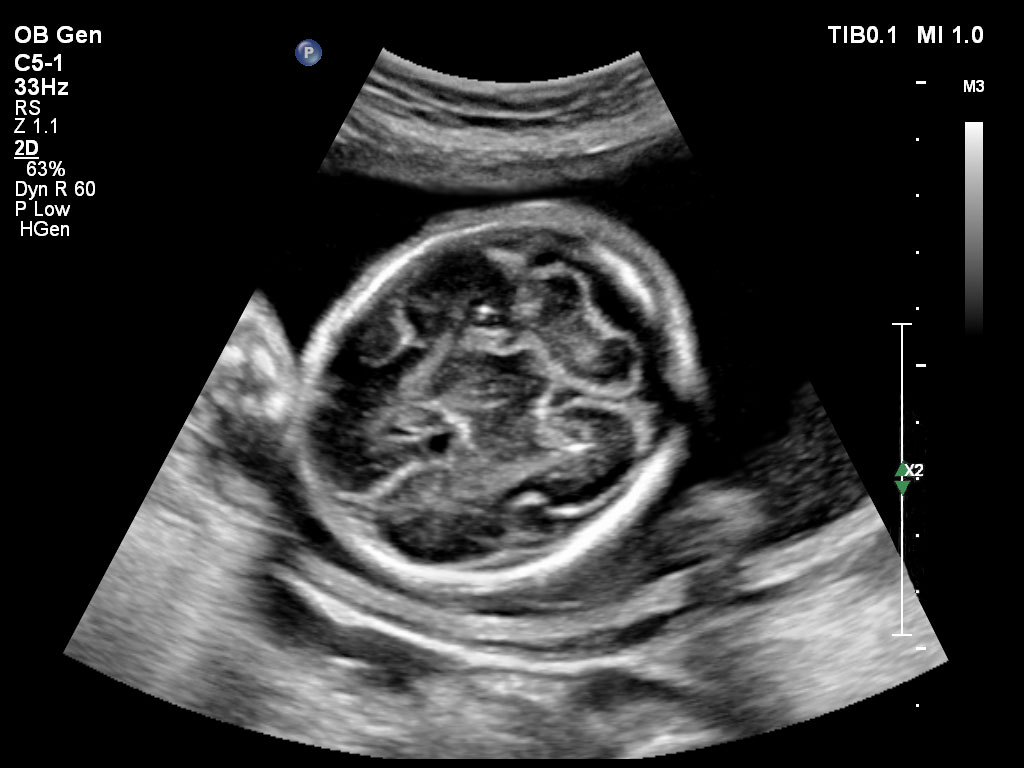

Die EPIQ-Produktreihe mit ausgereiften Schallköpfen erfüllt die Anforderungen auch Ihrer anspruchsvollsten gynäkologischen Untersuchungen und während der gesamten Schwangerschaft.

• C5-1 PureWave-Breitband-Convex-Schallkopf für hohe Eindringtiefen in der Gynäkologie und der Geburtshilfe, für Patientinnen mit Schwangerschaftsdiabetes oder vorzeitigem Blasensprung